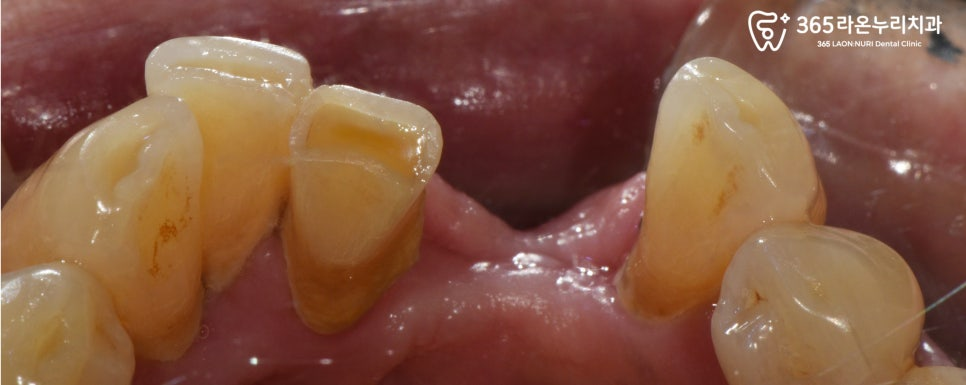

아래턱 역시도, 치조골이 많이

내려가게 되면서 치아 뿌리쪽이

많이 드러나고 있었습니다.

엑스레이를 보시면 전체적으로

치아 뿌리가 드러날 정도의

골소실이 일어나 있는 것을

더욱 명확하게 확인할 수 있었는데요.

보시는 것과 같이

잇몸뼈가 뿌리 끝까지 녹아

더이상 치아를 지지하지

못하고 흔들리고 있었는데요.